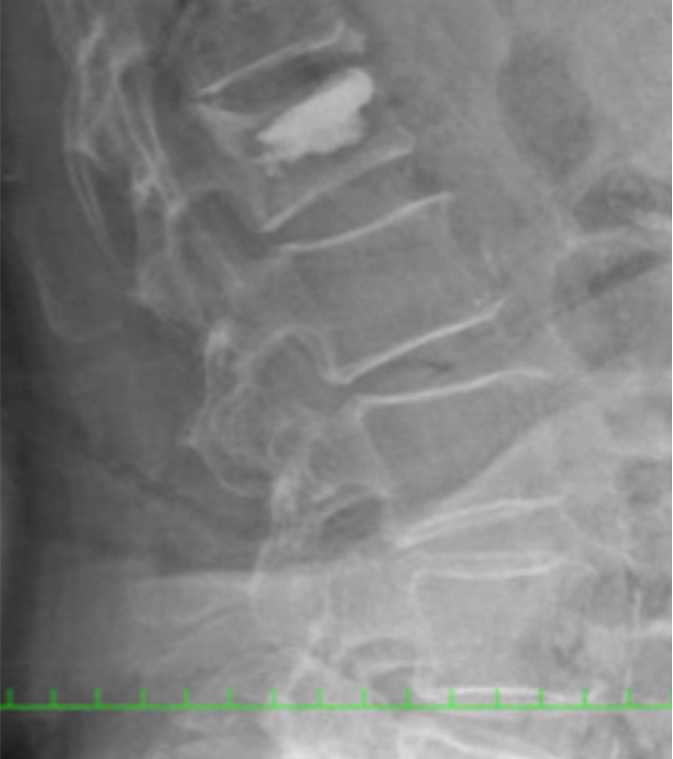

日本,骨质疏松症的人群成为老龄化社会已经说是显著上升到10多万。伴随着的是,它也已成为谁在轻微外伤和日常生活的操作经历脊柱压缩性骨折的病人越多。作为初始治疗,休息,口服中药,紧身胸衣,保守治疗,如恢复完成后,你有良好的临床效果不能获得。在另一方面,获得不够保守,尽管治效果果,变成了假关节(其中骨不完全愈合的状态),疼痛也有剩余的情况下。这样,对于因脊椎骨折剩余的痛苦,我们有各种各样的手术。

引起的原发性骨质疏松椎体压缩性骨折,改编已执行积极BKP(由气球皮椎体成形术),如果有的话。

在全身麻醉的风险案件或案件之外的BKP适应,具有在局部麻醉下一个PVP(经皮穿刺椎体成形术)与我院放射科协作去协同放射科。

在比BKP或PVP其他操作,它是融合,并用人造骨经皮椎弓根螺钉或HA(羟基磷灰石)椎体成形术的组合。